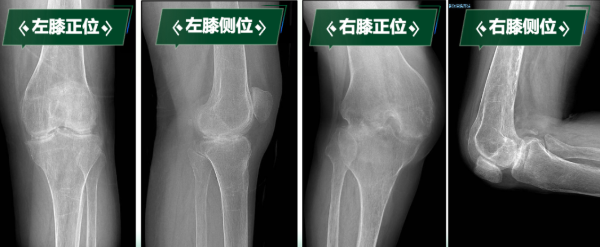

“真不敢相信,我能站起來,還能走路……”劉阿姨因罹患類風濕性關節(jié)炎多年,骨質(zhì)受到嚴重侵蝕,導致雙膝關節(jié)逐漸纖維性強直,更加棘手的是,雙膝強直于兩個極端體位,左膝關節(jié)無法彎曲,像“木棍”一樣始終處于伸直狀態(tài);右膝長期處于極重度屈曲攣縮90度無法伸直。這種“一伸一屈”的特殊畸形,導致無法正常坐立、行走,生活無法自理,身心承受巨大痛苦……

下肢處于功能“鎖死”狀態(tài)的劉阿姨,不僅被剝奪了行走能力,還導致嚴重肌肉萎縮、骨質(zhì)疏松,生活質(zhì)量急劇下降,手術是幫助她重新站起來的唯一途徑。科室高度重視,經(jīng)多學科會診討論,制定周密治療規(guī)劃。曹曉瑞副主任醫(yī)師團隊分析術前影像學資料,精確評估膝關節(jié)骨質(zhì)破壞、關節(jié)融合及周圍軟組織條件。

手術關鍵難點在于精準截除融合骨組織、獲得屈伸間隙平衡、恢復下肢力線、確保韌帶平衡以重建膝關節(jié)功能。團隊憑借豐富經(jīng)驗和嫻熟技術,成功實施雙側人工全膝關節(jié)置換術。術后影像學檢查顯示,假體位置精準,下肢力線完美糾正,原本僵硬關節(jié)被活動自如的人工關節(jié)取代,患者功能恢復理想,能正常行走,生活質(zhì)量顯著改善。